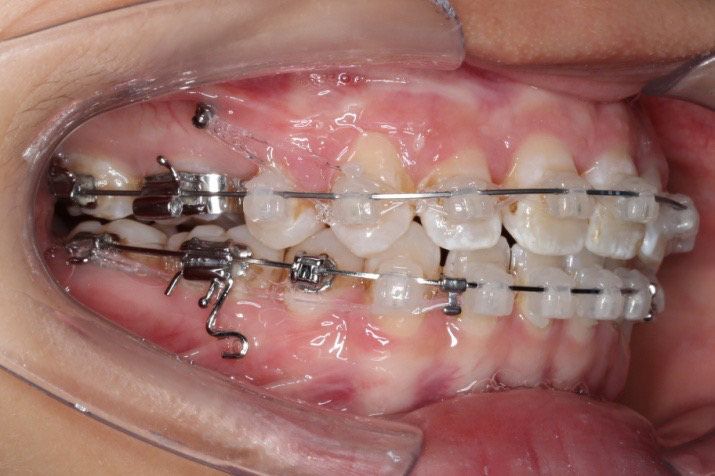

2016.10.31  初戴,0.013cu-niti2017.1.13  上颌加TPA,U56间斜形植入韩国庆北1312-08种植钉,上下0.16cu-niti

2017.02.16  上下0.014*25 cu-niti,50g 拉尖牙远中

2017.04.28

2017.04.28  上0.016*25ss 13、23近远中约5度 v形曲,下0.017*25ss

2017.05.26  磨牙近中倾斜,下颌36、46加power arm

2017.07.25

2017.07.25  上前牙加颈部弹力线